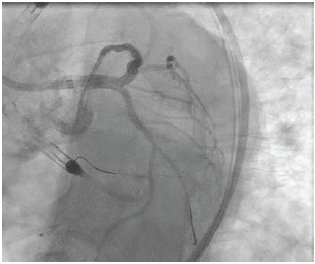

Yes, there are various axes of considerations. One that is commonly discussed is whether mechanical support is needed. Here we are really lacking in data and it comes down to judgment on the part of the operator. We have to take into account the ejection fraction, as well as hemodynamics and filling pressures regardless of the ejection fraction. Is there severe left main bifurcation disease that requires rotational atherectomy or is this just a simple ostial left main lesion? All of that goes into the hemodynamic concerns. For bifurcation technique, is it reasonable to use a provisional technique or do you need a two-stent technique? If so, what should that be? The best data we have support DK crush as the typical routine approach to the bifurcation. And then, of course, intracoronary imaging. We don’t have a lot of data specifically for the left main, but we know from many randomized trials with complex coronary disease, broadly defined, that people do better after PCI using intracoronary imaging. The data are overwhelming at this point. Technique is important, however, with optical coherence tomography (OCT) or intravascular ultrasound (IVUS). What exactly did you do with the data? My own practice has evolved significantly. We took part in a project called LightLab where a clinical field engineer was present in the cath lab with us. During angiography, not just for a left main, but for any PCI we were doing, we would estimate, based on the angiogram, the reference vessel diameter distally and proximally, the lesion morphology, and the lesion length, among other variables. Then we would do OCT and repeat the same evaluation. It was humbling to realize how difficult it is to be accurate with an angiogram alone. Today, that pre-PCI OCT or IVUS is hugely important. You can plan the entire procedure. You know how big the vessel is supposed to be, you know what the 1-to-1 balloon is and can see if the balloon is expanding appropriately. The historical view of imaging is that it is something done at the end of the procedure to check your work. The modern view is very different. You do intravascular imaging up front, plan your procedure and execute it, and then, on the back end, use it to make sure you have obtained the expected result.